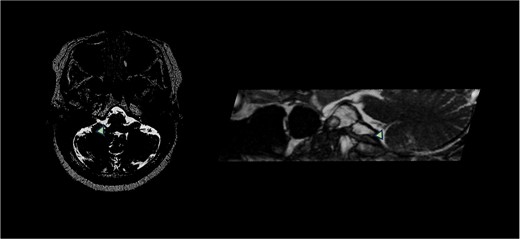

A 58-year-old female presented to neurosurgery with severe right-sided facial, tongue, and jaw pain unresponsive to multiple conservative therapies including medication. T2-weighted MRI with FIESTA sequence demonstrated right PICA compression of the right glossopharyngeal nerve entry zone (Fig. 1).

T2-weighted MRI with FIESTA sequence demonstrated right PICA compression of the right glossopharyngeal nerve entry zone demonstrating the axial and sagittal view. Arrow demonstrates location of neurovascular compression.